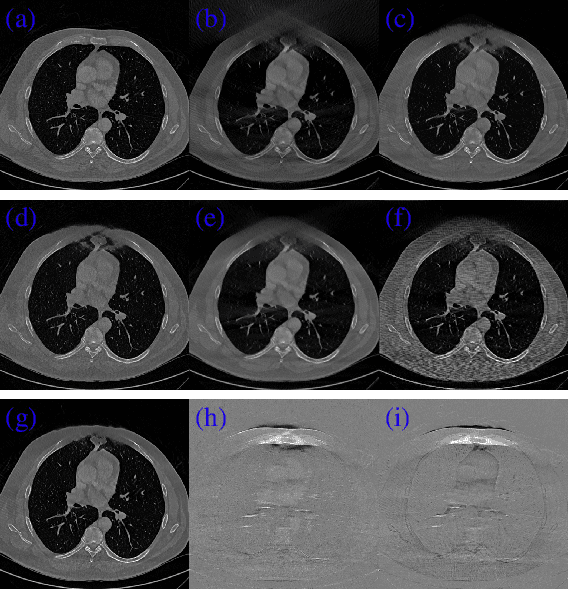

CT image reconstruction from incomplete data, such as sparse views and limited angle reconstruction, is an important and challenging problem in medical imaging. This work proposes a new deep convolutional neural network (CNN), called JSR-Net, that jointly reconstructs CT images and their associated Radon domain projections. JSR-Net combines the traditional model based approach with deep architecture design of deep learning. A hybrid loss function is adopted to improve the performance of the JSR-Net making it more effective in protecting important image structures. Numerical experiments demonstrate that JSR-Net outperforms some latest model based reconstruction methods, as well as a recently proposed deep model.